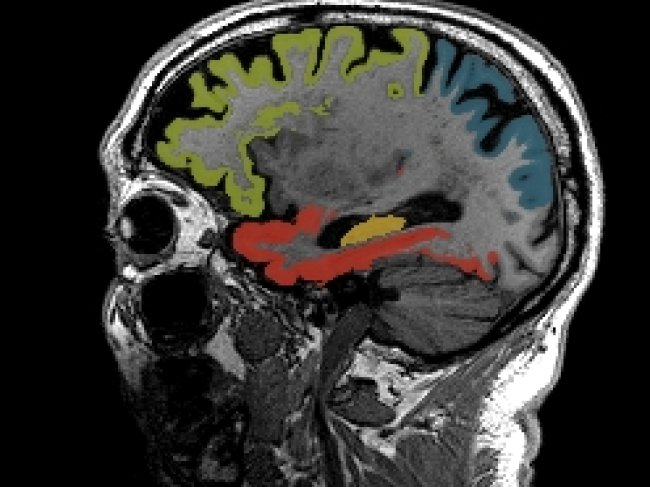

Inteligência Artificial ao serviço da Neurologia

Esta solução de inteligência artificial (IA), especializada na análise de exames neurológicos, permite uma avaliação mais detalhada e objetiva de imagens de ressonância magnética e tomografia computorizada do cérebro.